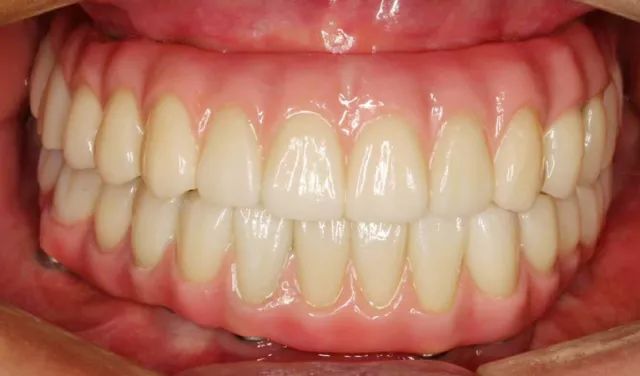

精彩案例: